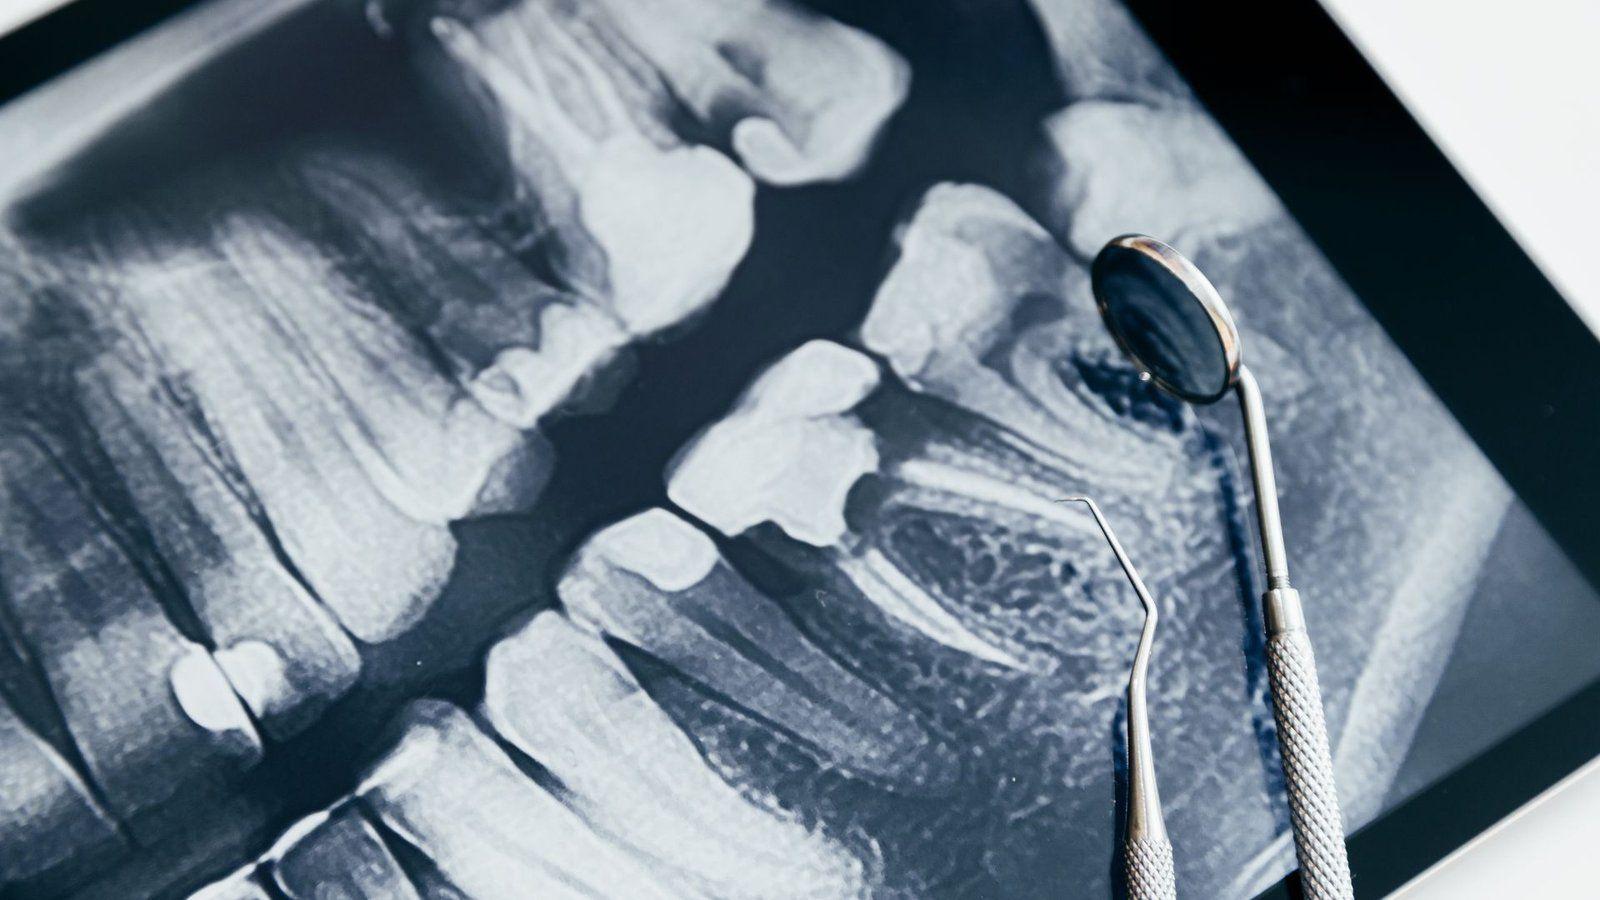

Discover the importance of dental x-rays for comprehensive dentistry. Learn how these services contribute to maintaining optimal oral health. As part of comprehensive dentistry, it play a crucial role in diagnosing and treating various oral health issues. From detecting hidden dental problems to planning treatments, these services provide valuable insights into the overall oral health…